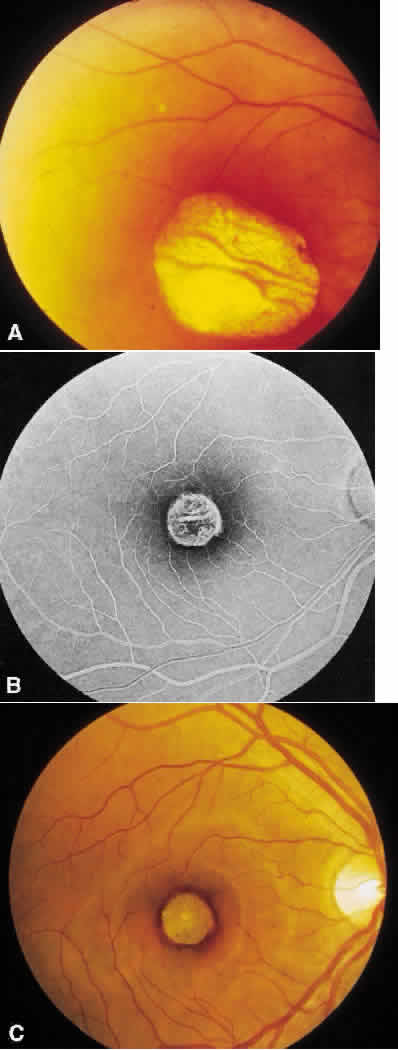

Central areolar choroidal dystrophy is characterized by a well-circumscribed atrophy of the RPE and choroidal vessels confined to the macula and unassociated with any other causes for chorioretinal atrophy.64,65 A fluorescein angiogram will clearly show choriocapillaris atrophy with diminished background choroidal fluorescence and persistentvisualization of the larger choroidal vessels, even when the atrophy is not apparent funduscopically (Fig. 5).66

Fig. 5. Central areolar choroidal dystrophy. A. There is a well-circumscribed macular sheen surrounded by a hyperpigmented border but no evidence of choroidal atrophy in this 23-year-old man. B. The angiogram indicates some degree of choriocapillaris atrophy since there is persistent visualization of the choroid vessel. C. As the lesion progresses, as is seen in this 62-year-old woman, the well-circumscribed area of chorioretinal atrophy overlying the bare sclera is easily seen.

With progression of the disease, the chorioretinal atrophy is obvious, and in the late stages, a few large choroidal vessels may be seen coursing over the white sclera. The yellowish appearance of these vessels prompted the conjecture that choroidal vas-cular “sclerosis” was the primary cause. However, histopathology has clearly shown no evidence of vessel wall sclerosis, but rather a well-delineated macular zone of atrophy of the choriocapillaris.67–70